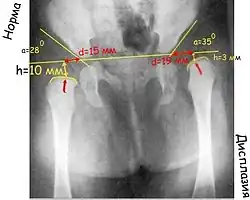

Большая часть головки бедра и вертлужной впадины у детей раннего возраста состоит из хрящей, которые невидимы на рентгеновском снимке, поэтому для чтения рентгенограмм применяют различные схемы.

Прежде всего проводят вертикальную срединную линию, она проходит через середину крестца. Проводят горизонтальную линию через У-образные хрящи, через нижние точки подвздошной кости (линия Хильгенрейнера). Через наружно верхний край, перпендикулярно горизонтальной линии проводят линию Перкина. Часто бывает, что на стороне поражения невозможно определить верхний край вертлужной впадины. В этих случаях пользуются методом Рейнберга: симметрично, на таком же расстоянии от срединной линии проводят вертикальную линию (перпендикулярно горизонтальной). Она и будет обозначать невидимый на рентгенограмме верхнелатеральный край впадины. Через края вертлужной впадины проводят касательную линию до пересечения с горизонтальной линией Хильгенрейнера. Образованный угол называется «ацетабулярный угол», или угол наклона крыши вертлужной впадины.

К вспомогательным линиям относят линию Шентона и Кальве. Линия Шентона (запирательно-бедренная дуга) в норме «представляет собой мысленное продолжение краниального края запирательного отверстия на медиальный краевой контур шейки бедра» (В. О. Маркс, 1978). При патологии (смещении бедра латерально и вверх) эта линия разрывается.

При дисплазии ядра окостенения появляются позже, размеры их меньше, они развиваются медленнее. В норме ядро окостенения головки бедренной кости большей своей частью располагается медиальнее линии Перкина и ниже линии Хильгенрейнера. При подвывихе и вывихе она смещается вверх и латерально. Ядра окостенения головки бедра появляются у девочек в 4-месячном, у мальчиков в 6-месячном возрасте.

Величина ацетабулярного угла в норме составляет менее 30° у новорождённых и около 20° у детей от 3 месяцев и старше.

«У нормального новорождённого угол наклона крыши (ацетабулярный угол) равен в среднем 25–29°. Угол наклона у грудного ребёнка в связи с прогрессирующим окостенением таза от месяца к месяцу уменьшается. К одному году жизни угол равен в нормальных условиях у мальчиков 18,4, у девочек – 20,0°. К 5 годам жизни он бывает меньше 15,0° у детей обоего пола. Углы наклона крыши, превышающие средние цифры, означают задержку нормального окостенения, то есть ту или иную степень дисплазии сустава. Незначительные отклонения от нормы исчезают обычно в первые месяцы жизни младенца» (В. О. Маркс)

Очень важный показатель, характеризующий дисплазию тазобедренного сустава, — величина h, характеризующая вертикальное смещение головки бедра. Это расстояние от линии Хильгенрейнера до центра головки бедра, то есть примерно до середины видимой на рентгенограмме метаэпифизарной пластинки бедренной кости (на 1–1,5 мм выше).

В норме величина h составляет от 9 до 12 мм. Уменьшение этого размера или различие его справа и слева указывают на дисплазию.

И ещё один важный показатель – величина d – показатель латерального смещения головки бедра относительно вертлужной впадины. Это расстояние от дна вертлужной впадины до линии h. В норме он не превышает 15 мм.